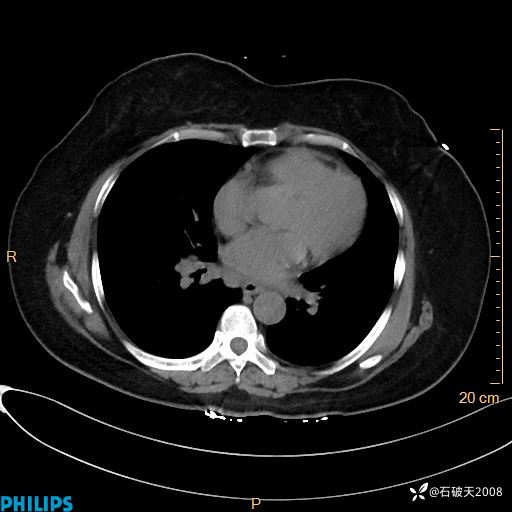

静脉期